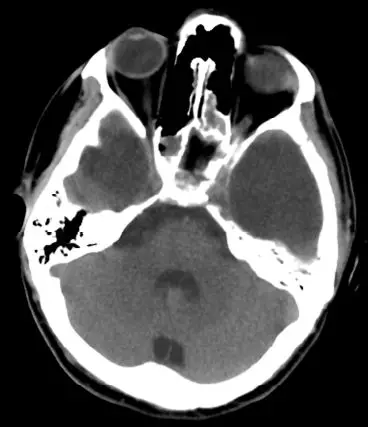

25岁男性患者,有双侧颞部蛛网膜囊肿,因醉驾而发生车祸。入院时GCS评分为15分,体格检查未见阳性体征;头颅CT和MRI提示双侧颞部蛛网膜囊肿的前端各有一颞部硬膜外血肿。左颞蛛网膜囊肿为4.8×5.4cm,右颞囊肿为3.1×3.7cm。左侧颞部EDH最大厚度3cm,右侧2.2cm;同时伴有横向的颞骨骨折(图1)。给予患者保守治疗。随后的CT复查显示EDH稳定(图2)。出院后3周,复查头颅CT显示,EDH明显吸收(图3)。

图1. 双侧颞部蛛网膜囊肿前端发生创伤性硬膜外血肿。A.头颅CT;B.MRI-T2加权像。

图2. 头颅CT复查。